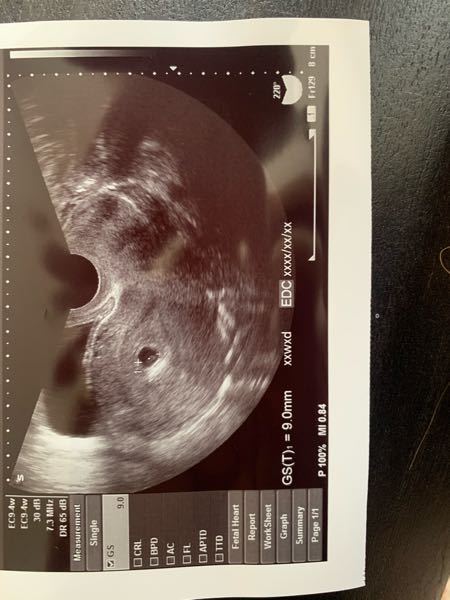

胎嚢確認できて良かった という安心感はあったけれど、 なんとなく大きさが気になってネットで検索しちゃうとね、 女医先生は「順調」って言ってくれたけれど、 前も5W6Dで9.8mmの胎嚢が · BT17 胎嚢確認 5w1d まずは数値から↓ E2 2267 P4 06 βHCG この日、朝茶色い出血があり焦る。 茶色だけど出血は出血どきどきしながら病院へ行きました。 結果、HCGが驚きの伸びを見せてくれました! そして胎嚢も無事確認!サイズは58mmと小さめ。 ネットでいろいろ見てると大きさが心配になるものの、とりあえずホッとしました 出血については、茶色胎嚢は、62mmでした。 夢クリの基準値(BT17)が510mmとの事でしたので BT18の判定という事を考慮すると かなりギリギリの数値ではありますが (この時期胎嚢は1日1mm成長) 何とか基準値内はクリアしてくれました。 先生からは

Bt17 胎嚢 大きさ 平均- · 胎嚢が小さいと言われた平均的な大きさは? 胎嚢の大きさには個人差があり、一概には言えませんが、妊娠5~8週の場合、「胎嚢最大径(cm)=妊娠週数4」という数値が一つの目安になります。 たとえば、妊娠6週頃であれば胎嚢の大きさはおおよそ2cmほど。この時期になると、そのなかに包まれている数mmくらいの赤ちゃん(胎芽)がエコーで見えることが · 2 5w0dで胎嚢確認平均サイズは72mm。5w0dの胎嚢の大きさをまとめました 5w0dの胎嚢の大きさをまとめました 結論:5w0d時点での 胎嚢の大きさの平均は、72mm です。

· いつも勉強させて頂いています。 体外で今回陽性判定になり、今BT21日目なのですが 胎嚢は10mmくらいしかなく、卵黄嚢もうっすらあるかないかのレベルで心拍まではまだ確認できていない状態です。BT9でhcg63、5日後で477と、出だしも遅く、ネットで検索しても今の大きさでは結果流産したとの0316 · 不妊治療 兆候 妊娠 妊娠5週目(5w4d)に、内診検査にて、ついに胎嚢が確認! 5週の胎嚢サイズの平均は1673mmなので、胎嚢は63ミリで小さい。胎嚢の大きさ・頭殿長の大きさ 胎嚢の大きさと妊娠数週は以下のとおりです。 胎嚢の大きさ・頭殿長の大きさの平均値がわかります。 最大胎嚢径 (GS) 頭殿長 (CRL) cm 平均 範囲 cm 平均 範囲 10 4w5d 4w2d5w2d 10 7w4d 7w1d8w1d 11 4w6d 4w3d5w3d 11 7w5d 7w2d8w2d 12 5w0d 4w3d5w4d 12 7w6d 7w3d8w3d 13 5w0d 4w4d5w5d 13 8w0d 7w4d8w4d